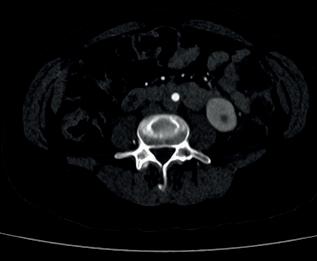

Left: Pre- and postoperative images (courtesy of Dittmar Böckler) of the first European implantation of the Gore Tag TBE; above: Dittmar Böckler performing the implantation